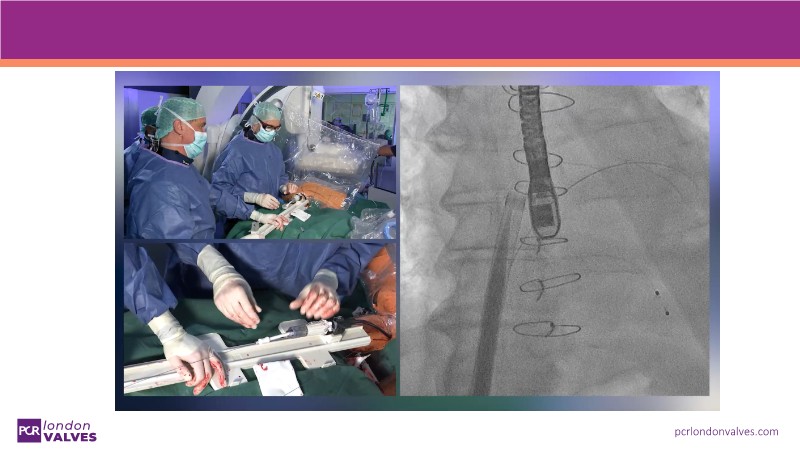

This session explores a full spectrum of therapeutic options for mitral and tricuspid regurgitation, focusing on the PASCAL Precision system for targeted repair and the SAPIEN M3 transcatheter mitral valve replacement. Through beating heart simulators, case discussions, and clinical evidence, participants will understand the versatility and unique features of these advanced interventions.

- To appreciate the unique features of SAPIEN M3 transcatheter mitral valve replacement system with an evidence update, live simulation and recorded case